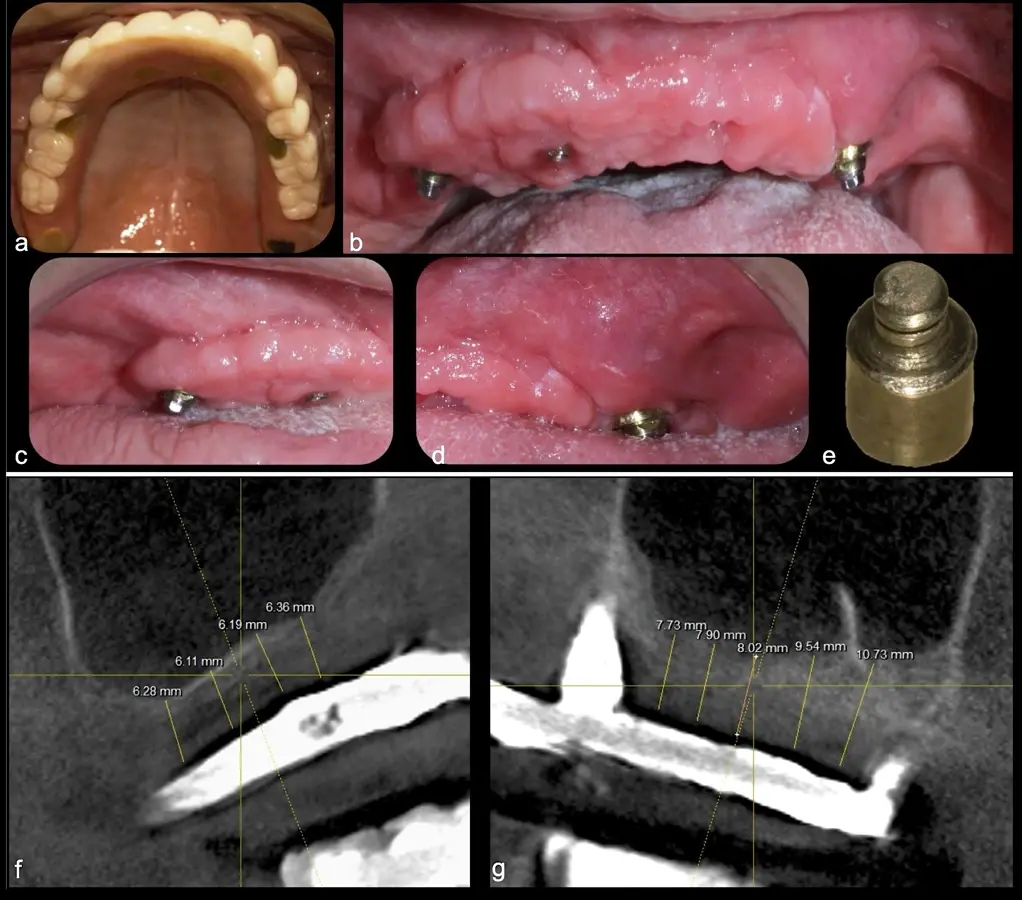

El levantamiento de piso de seno maxilar es una técnica quirúrgica aceptada previa o simultáneamente a la colocación de implantes dentales. La mayor evidencia científica refiere que si se tiene entre 0 -7 mm de altura ósea se debe realizar la elevación sinusal junto con injertos óseos; y a partir de los 8 mm, se hace más predecible la colocación simultánea de implantes dentales.1-3

Aunque esta técnica es predecible, la perforación de la membrana sinusal es la complicación intraoperatoria más común, con una prevalencia de hasta el 58.3%.4 Existen también otras complicaciones reportadas, como hemorragias asociadas a la lesión de la anastomosis arterial en el área de la pared lateral del seno maxilar.5-8

El clínico puede retirar la tabla ósea o introducirla como “tienda de campaña” dentro del seno maxilar. En cualquiera de las alternativas, es importante evaluar la presencia de tabiques óseos y de la arteria postero alveolar superior.